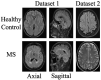

Multiple sclerosis (MS) is a chronic autoimmune disease of the central nervous system that prominently affects young adults due to its debilitating nature. The pathogenesis of the disease is focused on the inflammation and neurodegeneration processes. Inflammation is associated with relapses, while neurodegeneration emerges in the progressive stages of the disease. Magnetic resonance imaging (MRI) is commonly used for the diagnosis of MS, and guidelines such as the McDonald criteria are available. MRI is an essential tool to demonstrate the spatial distribution and changes over time in the disease. This study discusses the use of image processing techniques for the diagnosis of MS and specifically combines the MobileNetV2 network with exemplar-based learning, IMrMr feature selection, and K-Nearest Neighbors (KNN) classification methods. Experiments conducted on two different datasets (Dataset 1 and Dataset 2) demonstrate that these methods provide high accuracy in diagnosing MS. Dataset 1 comprises 128 patients with 706 MRI images, 131 MS patients with 667 MRI images, and 150 healthy control subjects with 1373 MRI images. Dataset 2 includes an MS group with 650 MRI images and a healthy control group with 676 MRI images. The results of the study include 10-fold cross-validation results performed on different image sections (Axial, Sagittal, and Hybrid) for Dataset 1. Accuracy rates of 99.76% for Axial, 99.48% for Sagittal, and 98.02% for Hybrid sections were achieved. Furthermore, 100% accuracy was achieved on Dataset 2. In conclusion, this study demonstrates the effective use of powerful image processing methods such as the MobileNetV2 network and exemplar-based learning for the diagnosis of MS. These findings suggest that these methods can be further developed in future research and offer significant potential for clinical applications in the diagnosis and monitoring of MS.